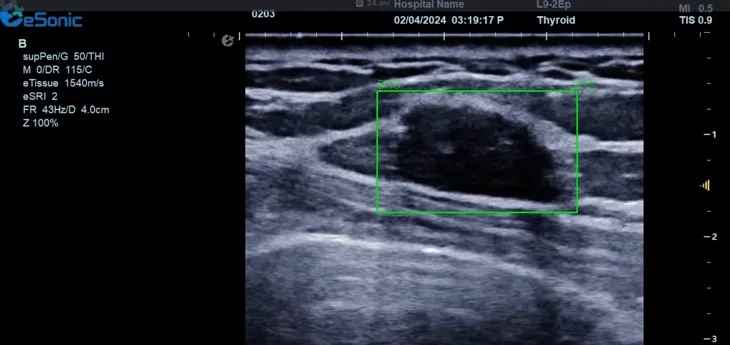

hjc888黄金城官网医疗(ESI)表示,其最新的人工智能功能可以帮助到医疗机构的工作效率,功能包括,实时、动态、快速自动识别病灶,良恶性病灶概率预测,甲状腺结节和乳腺的二维灰阶动态自动实时检测需求,提供多个结节动态检测轮廓框。实时获取多幅具备临床特征(大小、属性等)的结节切面,同时提供当前切面所示结节的结节大小、属性特征、TI-RADS 分级。

对于乳腺结节相关的自动检测功能,乳腺结节病灶检出率≥95%、良恶性分类灵敏度≥90%、良恶性分类特异度≥85%。